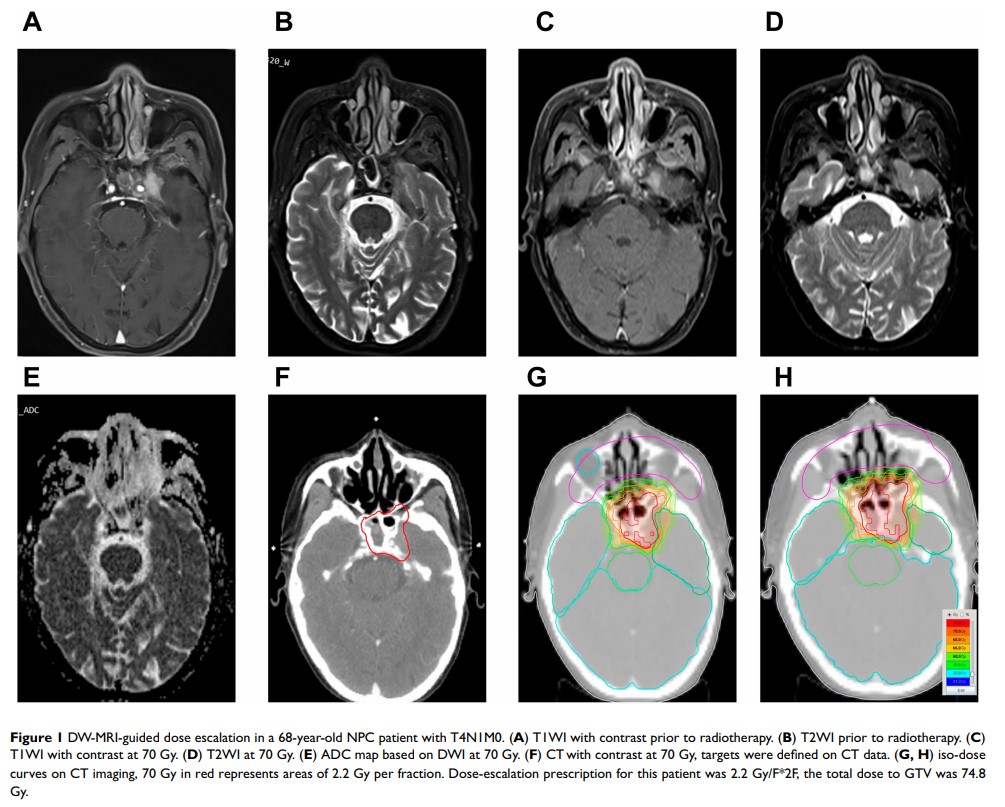

DW-MRI 引导剂量的增加使放化疗治疗的局部晚期鼻咽癌的局部控制得到改善